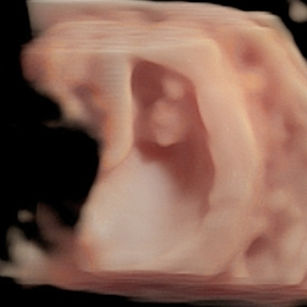

Tell Me About My Baby!

Size: ~0.6 inch (1.6 cm), the size of a Raspberry!

Development Highlights:

Baby is now called a fetus instead of an embryo.

Fingers and toes are forming, though webbed.

Facial features more defined: ears, eyelids, and nose.

Heart has four chambers and beats regularly.

8 Weeks Pregnant